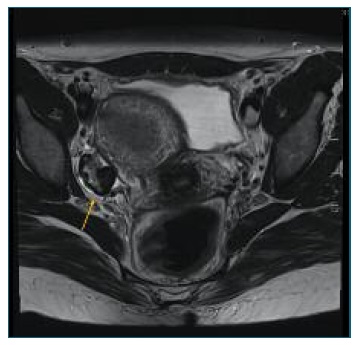

A 44-year-old woman, nulliparous, with regular menses and a personal history of primary Sjogren Syndrome, arterial hypertension, sinus bradycardia, hyperparathyroidism and androgenetic alopecia consulted her gynecologist to clarify a clinical condition of pelvic pain associated with an approximately 1cm heterogenous solid adnexal mass, Color Score 1 was found on ultrasound. Further characterization of the mass through MRI demonstrated moderate enlargement of the ovaries with lobulated margins. The ovarian cortex was thickened and demonstrated a homogeneous low-signal intensity on both T1 and T2-weighted images, suggestive of fibrous tissue, with a “black garland” appearance and consistent with ovarian fibromatosis.

Figure 1 Black garland Sign. Axial T2-weighted image demonstrating a markedly T2 hypointense rim around the ovaries (right adnexa showed) without a central ovarian parenchymal mass. This hypointense rim is referred to as the ‘‘black garland’’ sign.